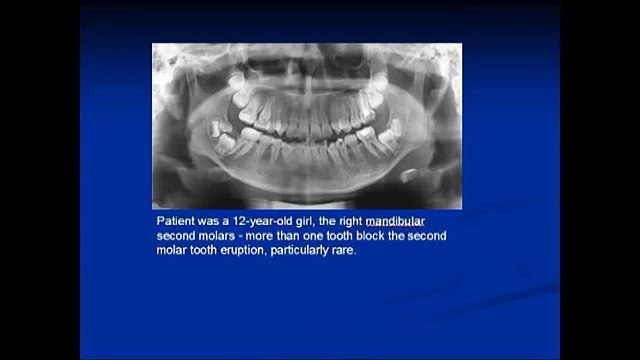

tooth, root, abscess, secondary, fractured, maxillary, horse, molar, removal